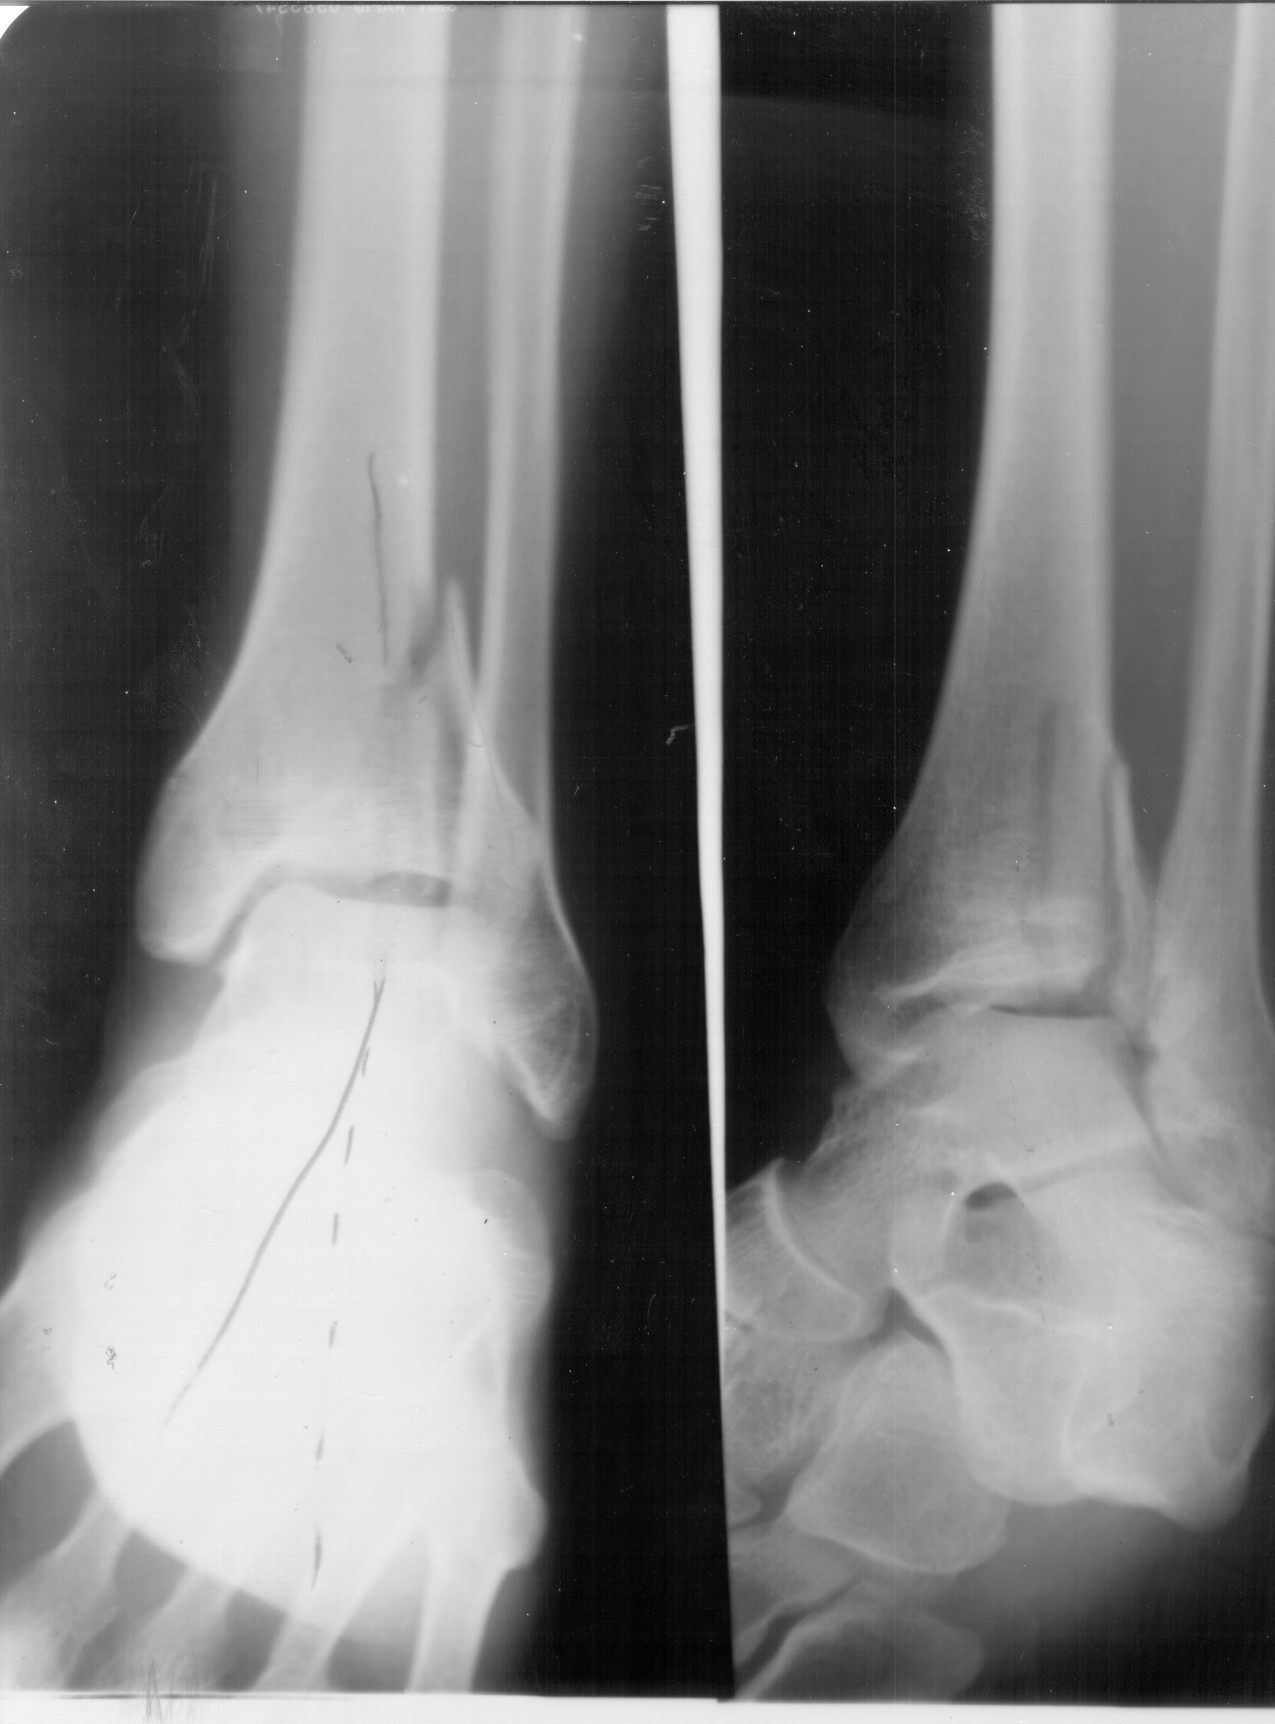

[IMG]xray1.jpg2020-01-26 20:40 251K